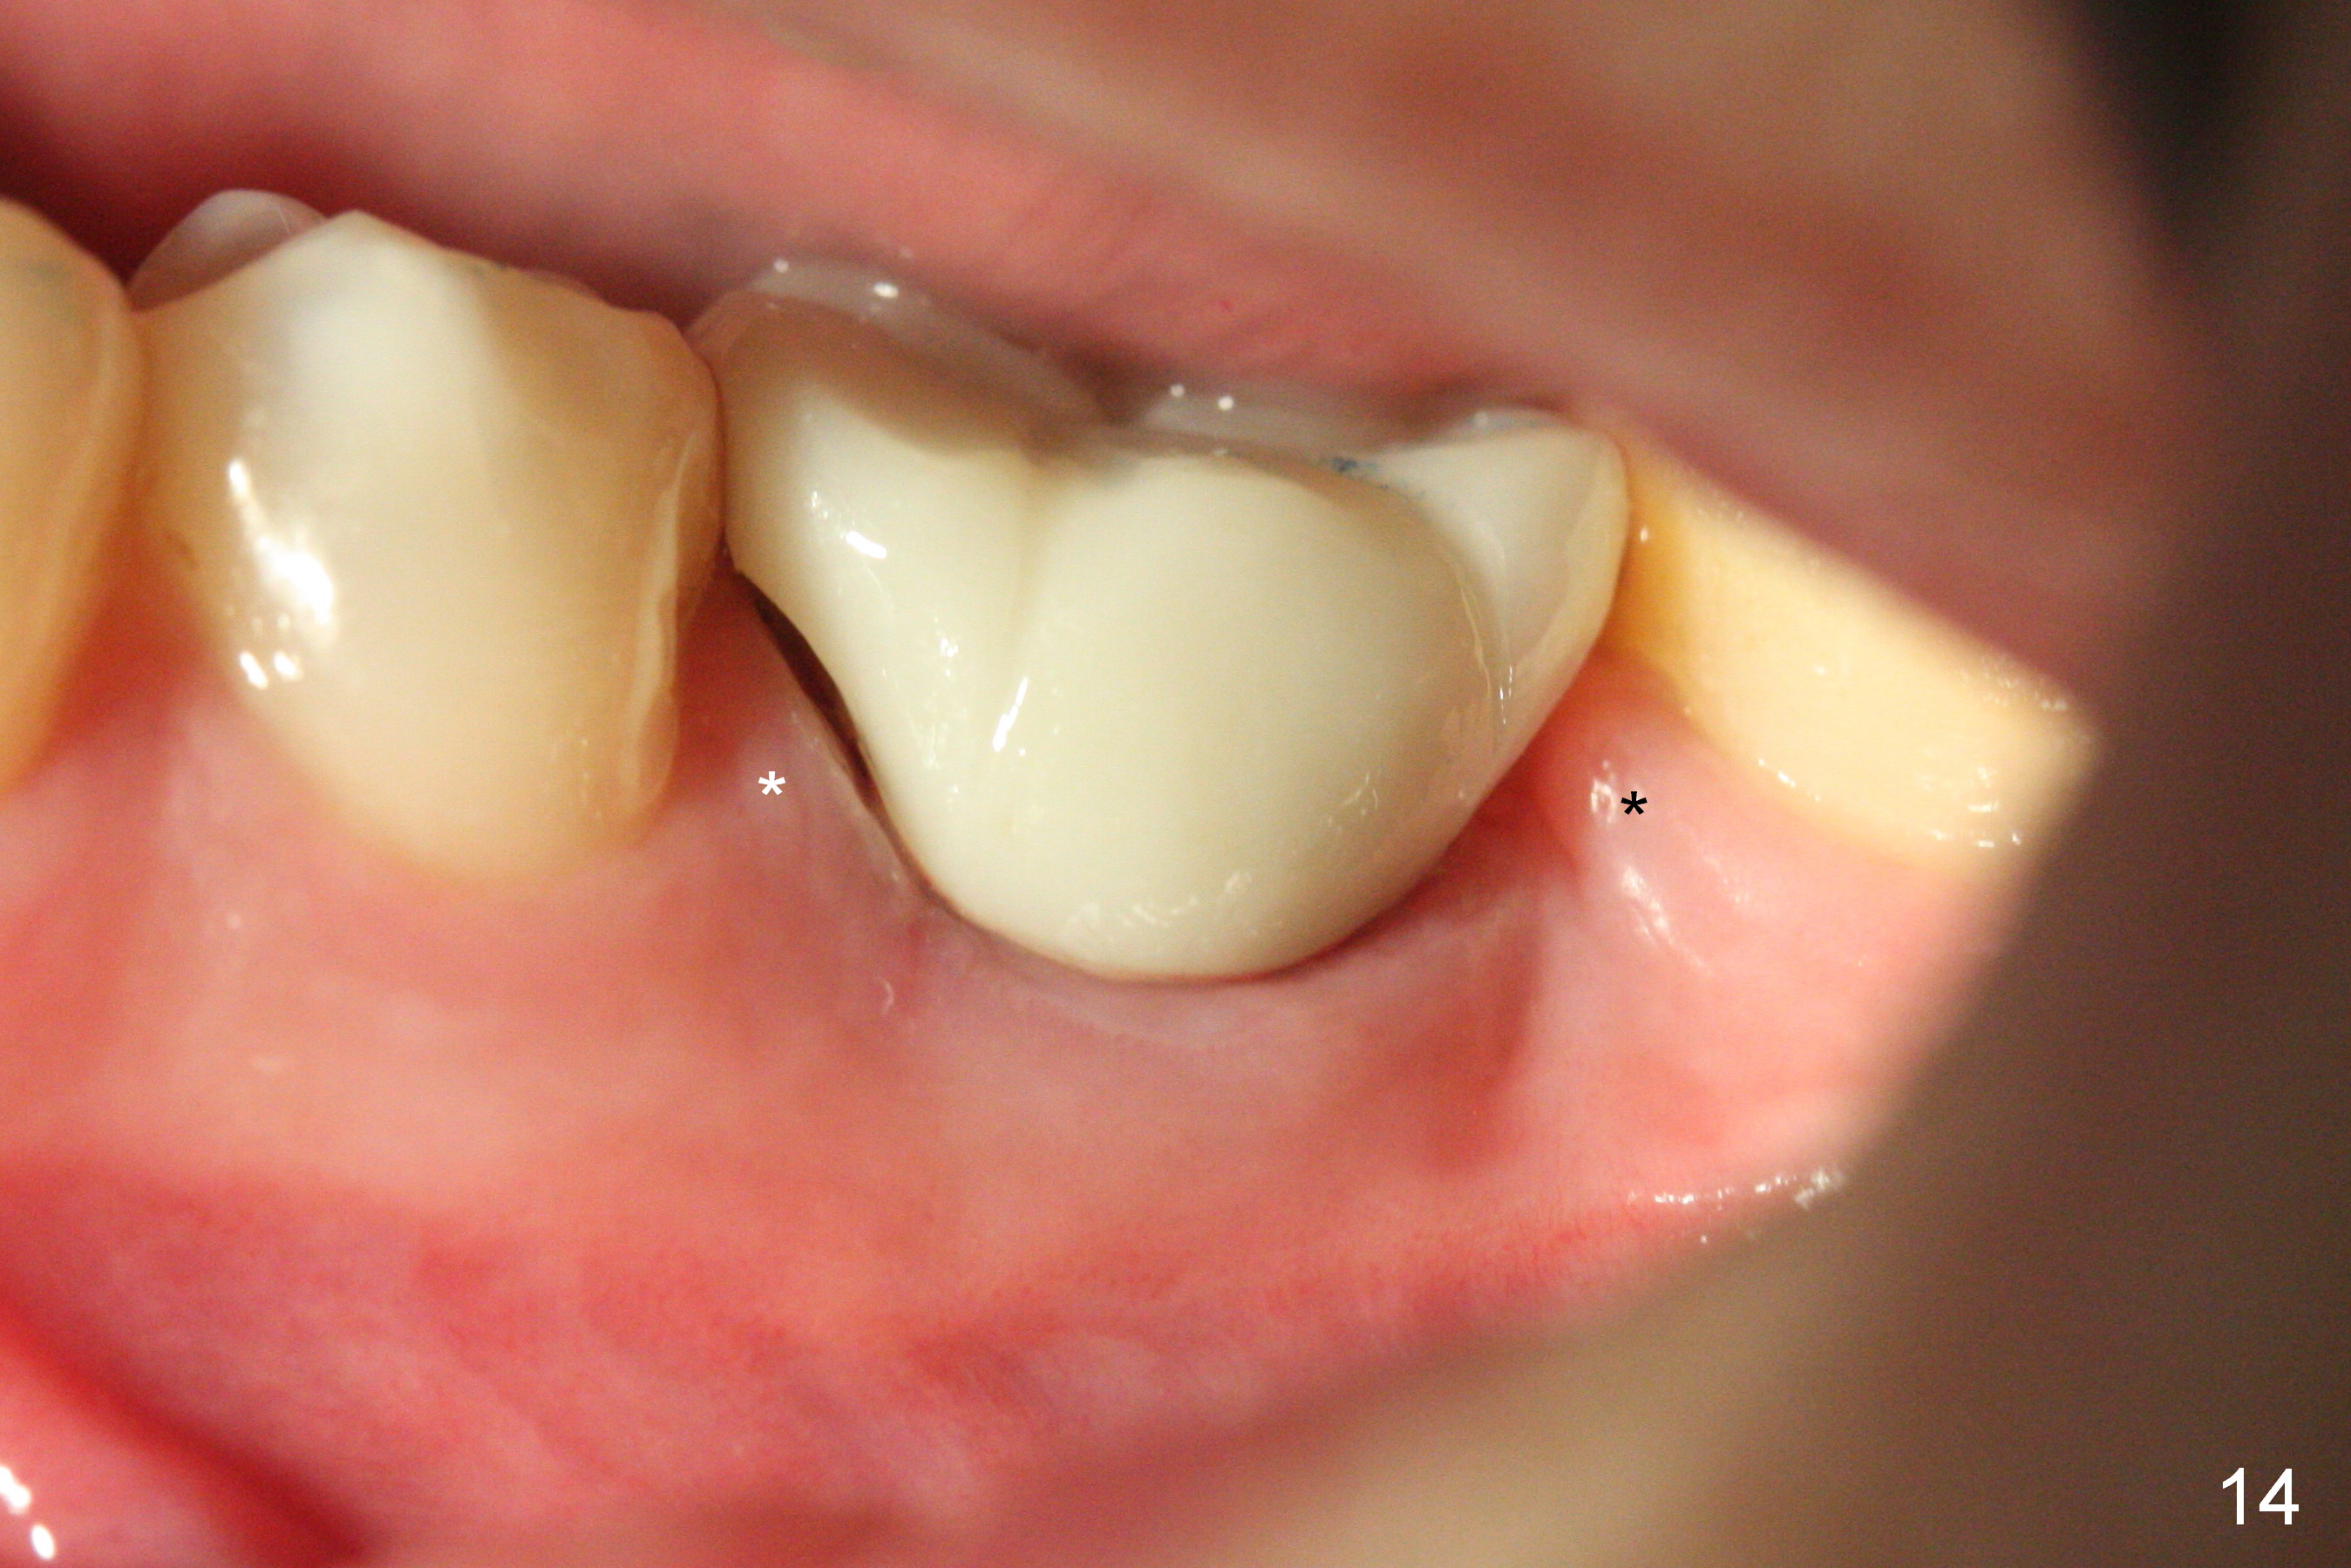

The Emax crown fractures 3.5 years post cementation; there is formation of the apparent lamina dura around the implant (Fig.13). There is no atrophy of papillae when the new crown is cemented (Fig.14 *). There is no bone loss nearly 4 years post cementation (Fig.15).